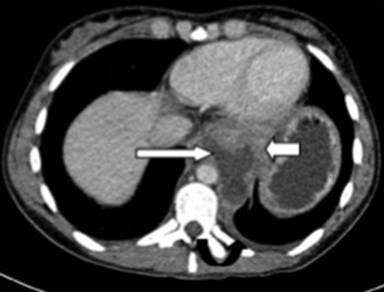

A twenty-two-year-old female with a history of alcohol-induced chronic pancreatitis was admitted with abdominal pain and dysphagia. On examination she had a midline laparotomy scar from previous abdominal surgery and marked tenderness in the epigastric area on palpation but the examination was otherwise unremarkable. Her blood tests revealed a white cell count of 14.0, haemoglobin of 11.7, platelets of 458, CRP of 4, amylase of 279, albumin of 39, bilirubin of 10, ALP of 93 and ALT of 21. Her urea and electrolytes were unremarkable. A CT scan performed during this admission revealed a large cyst arising from the body and tail of the pancreas extending posteriorly to the stomach and tracking behind the oesophagus and into the mediastinum (Figures 2 and 3). Cyst fluid aspirated under EUS guidance yielded an amylase level of 20,000 confirming this to be a pancreatic pseudocyst. The EUS also showed calcification in the pancreas in keeping with chronic pancreatitis. Although aspiration provided temporary resolution of her symptoms, the patient experienced recurrence of pain and discomfort. At laparotomy a retrogastric pseudocyst communicating with the mediastinum was clearly identified on intraoperative ultrasound scan. An anterior gastrostomy was performed and intraoperative ultrasound was again used to locate the pseudocyst. A posterior wall gastrostomy was created to enter the cyst and the cyst wall was sent for histology. Intraoperative contrast study confirmed the communication with the mediastinal cavity. A surgical cystogastrostomy and a feeding jejunostomy were performed. The patient had an uneventful recovery.

Figure 2. Case #2. Axial CT image acquired in portal phase following intravenous contrast medium. This demonstrates a well defined pseudocyst (long arrow) extending through the hiatus into the posterior mediastinum. The gastro-oesophageal junction (short arrow) is displaced anteriorly. There is a small reactive, non enhancing left pleural effusion (curved black arrow). |